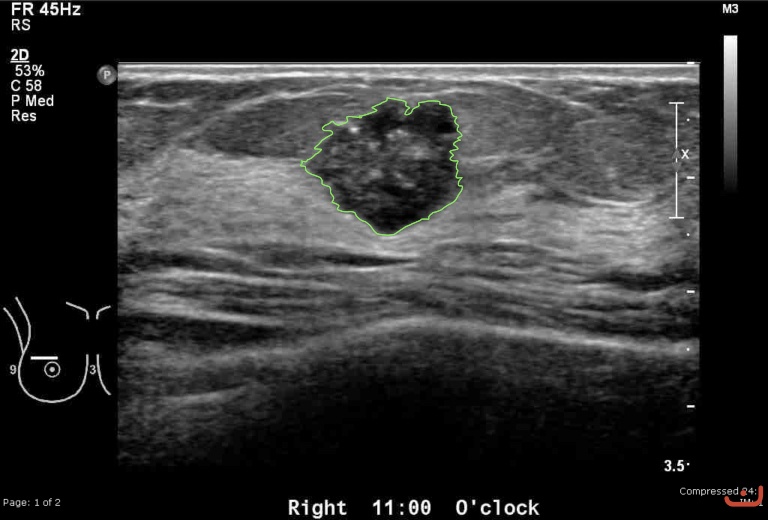

Case 34-G1

Malignant solid mass

Friday, 22 May 2015

168.18 KB (768 x 520 px)